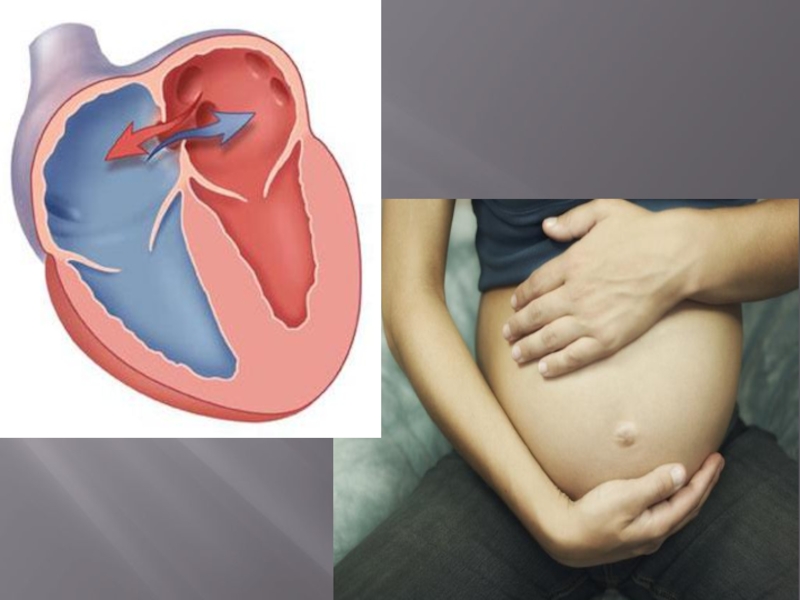

Фотографии и информация о приобретенных пороках сердца